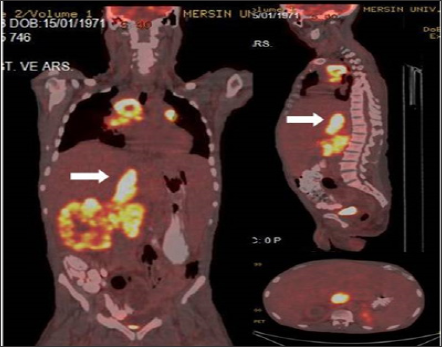

Figure 3: Coronal, sagittal and axial fusion images demontrate dilated VCI linear TT (SUVmax 16.88) with primary right RCC and widespread metastases in a 45 year old male patient.

FDG-PET/CT imaging performed for staging, restaging and treatment response in oncological patients and patients with suspected malignancy. A total of 37 patients with tumor thrombus and benign thrombus were included. Patients who had confirmed primary malignancies ( lung cancer in 7 patients, gastrointestinal and hepatobiliary malignancies in 13 patients, genitourinary malignancies in 8 patient, sarcoma in 2 patients, lymphoma in 1 patient, laringeal cancer in 2 patients or suspected malignancies in 4 patients) were undergone PET-CT imaging. The most common malignancy was lung cancer (Table 1). PET-CT imaging findings of a total of 37 patients with suspected tumor thrombus (25 men, 12 women, mean age: 53.62-range: 8-82) were evaluated retrospectively. Of the 37 patients 56 thrombus regions (45 benign and 11 malignant thrombus) were shown by PET-CT. A total of 8 (21.6 %) patients (7 M, 1 FM) with mean age 47.75 (Age Range: 8-69) were included in malignant thrombus group (Group I). A total of 29 (78.4 %) patients (14 M, 7 FM) were included in benign thrombus group (Group II). Two patients had more than one vessel, one of which had 3 and the other had 2 malign thrombus regions in group I. FDG uptake pattern was linear in 9 of the 11 segments and focal in 2 segments. (Figures 1-3) illustrates three demonstrative tumour thrombus patients' PET-CT images. Tumor thrombus in 11 segments in 8 patients and benign thrombus in 45 regions in the other 29 patients were reported in the evaluation of a total of 56 thrombi region in 37 patients on visual analysis and according to the increased metabolic activity. Various vessels were affected. The most common region of thrombosis was defined as vena cava inferior. SUVmax values ranged from 7.91 to 20 (mean:12.8) in 8 tumor thrombus patients. Compared to mediastinal region increased metabolic activity was not detected in none of the 29 patients with benign thrombus and these patients were treated with anticoagulant agents.